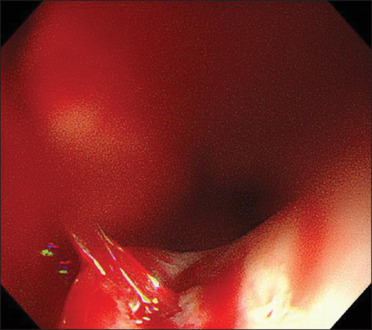

An aberrant right subclavian artery (ARSA) is a rare developmental anomaly wherein the right subclavian artery arises from the descending aorta as a fourth branch of the aortic arch. We present the case of ARSA in an 81-year-old woman who was injured in a motorcycle accident. The patient had a history of asymptomatic cerebral infarction, type 2 diabetes mellitus, and rheumatoid arthritis. She was diagnosed with spleen and liver injury, left renal injury, along with fractures in the rib, pelvic, vertebrae, and right tibia. On the 3rd hospitalization day, activated partial thromboplastin time (APTT) prolongation was observed, followed by sudden massive hematemesis and shock on the 39th day. We indicate sudden hematemesis and ARSA bleeding as the cause. We performed compression with a Sengstaken-Blakemore tube and coil embolization for hemostasis. Our findings show that the bleeding was mainly caused by nasogastric tube compression, prolonged APTT, and acquired hemophilia A.

畸形右锁骨下动脉(ARSA)是一种罕见的发育异常,即右锁骨下动脉从降主动脉发出,成为主动脉弓的第四分支。我们介绍了一例在摩托车事故中受伤的 81 岁女性的 ARSA 病例。患者有无症状脑梗塞、2 型糖尿病和类风湿性关节炎病史。她被诊断为脾脏和肝脏损伤、左肾损伤,以及肋骨、骨盆、椎骨和右胫骨骨折。住院第 3 天,观察到活化部分凝血活酶时间(APTT)延长,随后在第 39 天突然出现大量吐血和休克。我们指出突然吐血和 ARSA 大出血是病因。我们用 Sengstaken-Blakemore 管进行压迫,并用线圈栓塞止血。我们的研究结果表明,出血主要是由鼻胃管压迫、APTT延长和获得性血友病A引起的。